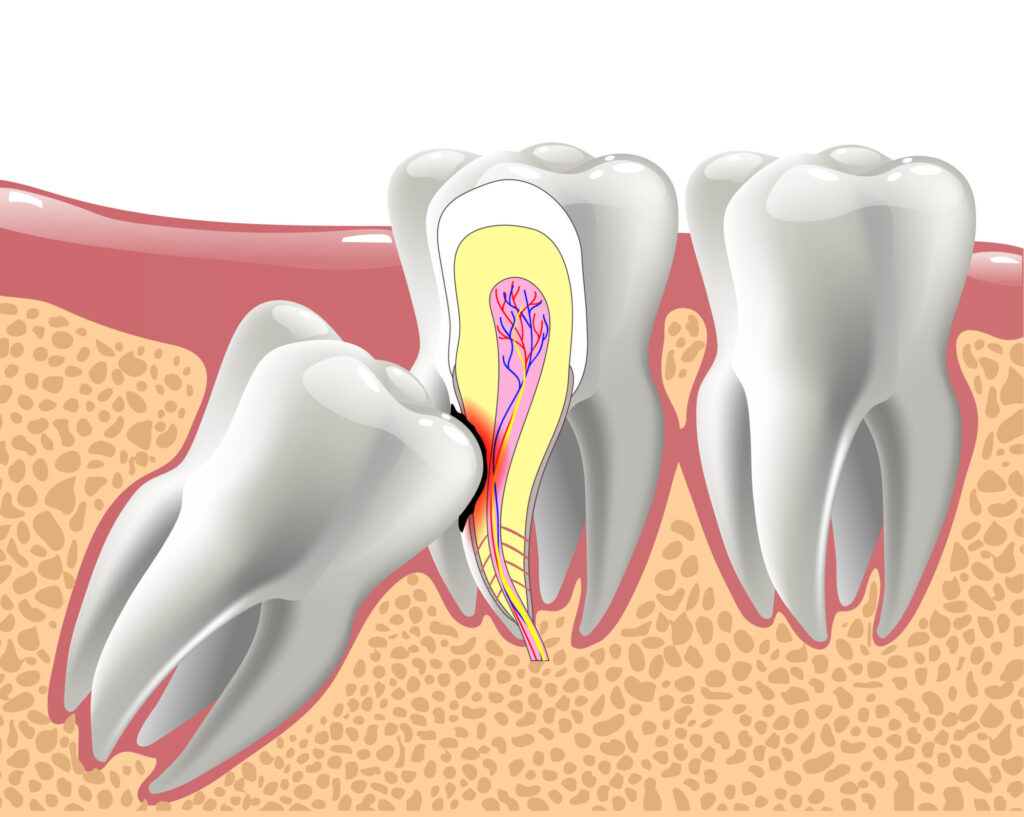

When there is not enough room for the tooth to erupt fully and in the correct position, it becomes impacted. An impacted wisdom tooth may grow sideways, at an angle, or remain completely buried beneath the gum.

Each type of impaction carries its own set of risks and complications. Some can damage neighboring teeth, while others create pockets where bacteria thrive.

Impacted or partially erupted wisdom teeth create a long list of potential dental issues.

They can press against the second molar, causing pain, shifting, or damage to that tooth. The tight space is also difficult to clean, which dramatically increases the risk of cavities and gum disease.

Partially erupted teeth create a flap of gum tissue called an operculum. Food and bacteria collect under this flap, leading to a painful infection called pericoronitis.